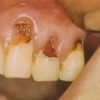

Hamba erosioon

Muu kui katubakterite happe põhjustatud hamba kõvakoe happelist kahjustust nimetatakse erosiooniks. Hape söövitab ehk demineraliseerib hambapinda, muutes selle pehmeks ja nii kiiresti kuluvaks.